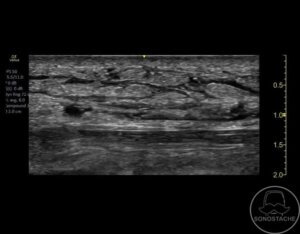

Case 9 – Cellulitis